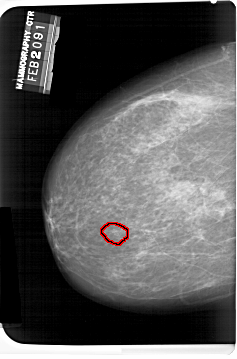

FILE: A_1407_1.LEFT_MLO.OVERLAY

TOTAL_ABNORMALITIES 1

ABNORMALITY 1

LESION_TYPE CALCIFICATION TYPE PLEOMORPHIC DISTRIBUTION CLUSTERED

ASSESSMENT 4

SUBTLETY 3

PATHOLOGY BENIGN

TOTAL_OUTLINES 1

LEFT_MLO LINES 6121 PIXELS_PER_LINE 4336 BITS_PER_PIXEL 12 RESOLUTION 43.5 OVERLAY